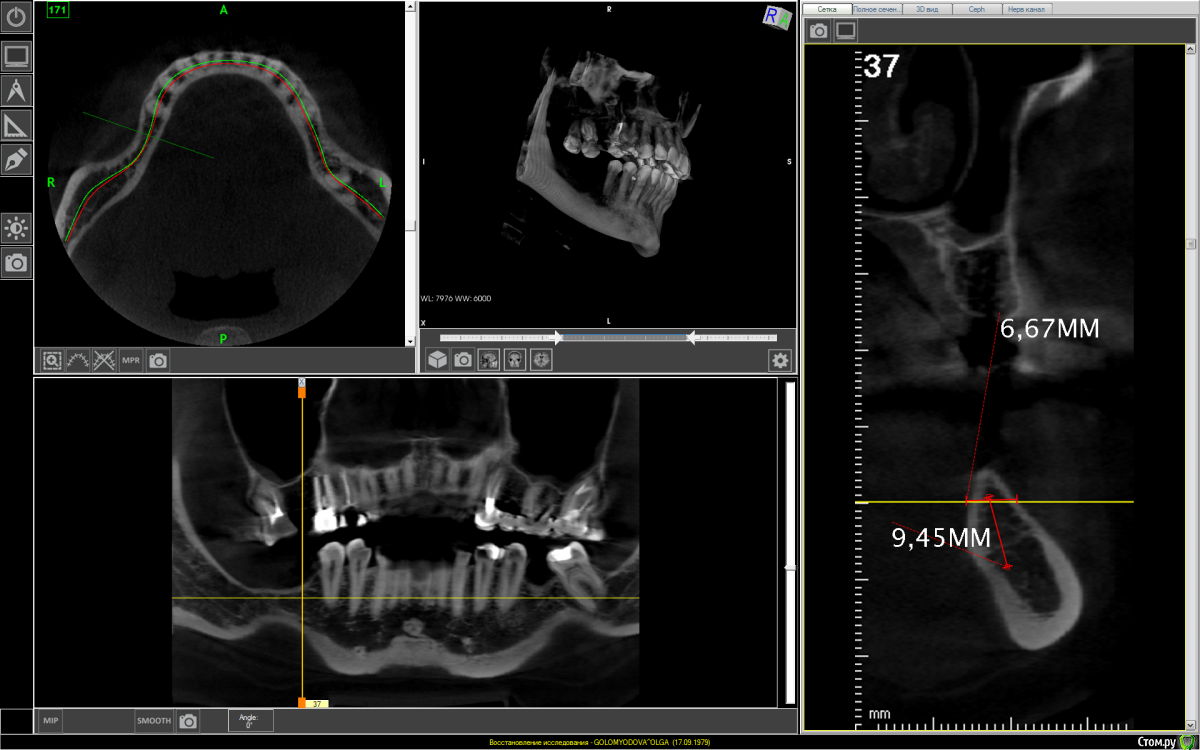

It'sGeorgy Опубликовано 26 февраля, 2021 Поделиться Опубликовано 26 февраля, 2021 1. Нет никакого смысла заниматься низом справа, если вы не будете заниматься верхом справа.2. Ситуация непростая, но я за имплантаты 8мм. + 6мм. с полированной шейкой. Посмотрим, что другие здешние коллеги еще подскажут. 2 Ссылка на комментарий

It'sGeorgy Опубликовано 27 февраля, 2021 Поделиться Опубликовано 27 февраля, 2021 (изменено) Спасибо за мнение!Значит можно без костной пластики обойтись?Если бы вы были моей пациенткой - я бы не стал вам рекомендовать зи проводить костную пластику. В плане ширины кости особых проблем у вас нет. Есть серьезная проблема в недостатке высоты костной ткани. Вертикальная костная пластика, точнее, ее отдаленные результаты - вопрос дискуссионный. Есть исследования, подтверждающие невысокую выживаемость результатов вертикальной пластики, но так же есть и доктора, которые демонстрируют хорошие и стабильные результаты. Здесь я на стороне первых.Но и здесь нужно понимать, что есть определенные риски: коронки на имплантатах будут в почти два раза больше в высоту, чем сами имплантаты. Есть мнения, что это плохо и создаётся рычаг. Резюмируя повторюсь: выбирая из этих двух рисков, я бы выбрал вариант с одним имплантатом 8мм и одним коротким 6мм с полированными шейками.Само собой, что установку таких имплантатов я бы проводил только по шаблону. И такая операция была бы возможно только при полной реабилитации жевательной эффективности: надо так же работать сверху справа и снизу слева. Изменено 27 февраля, 2021 пользователем It'sGeorgy 1 Ссылка на комментарий